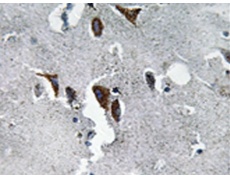

IHC positive control: |

Human brain tissue |